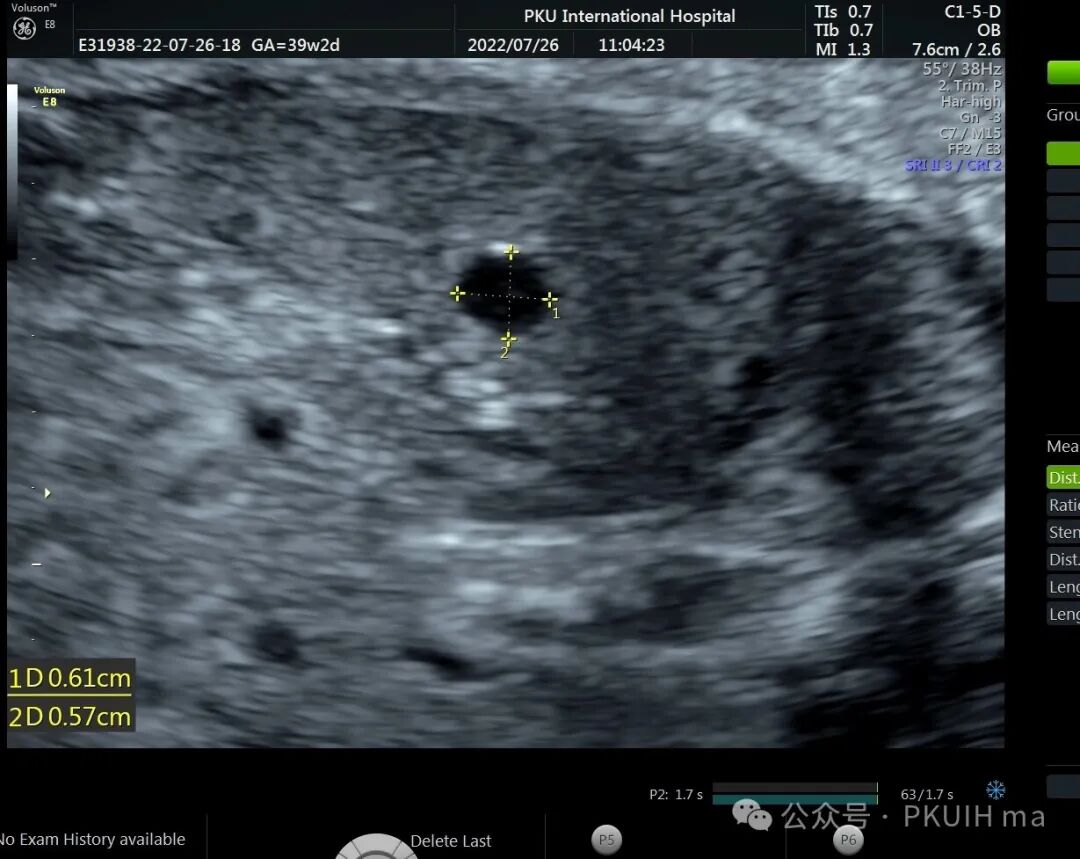

上两张图(第二张是37周)是一例在30周发现的肝囊肿,在随后观察中囊肿一直无变化